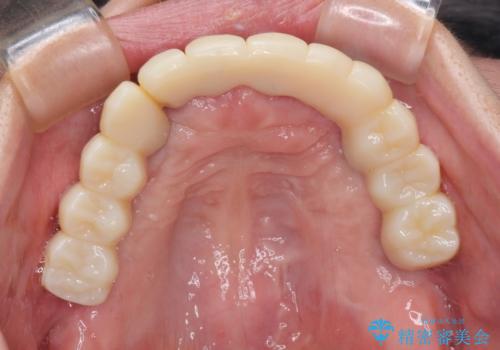

歯を抜かないといけない部分はインプラントとオールセラミッククラウンにより咬合を回復させ、歯周外科処置を行う歯については、同じくオールセラミッククラウンにて補綴治療を行うこととしました。

外科処置を多く行ったため、その待ち時間が長くかかり、さらには途中矯正治療も行なったので、治療期間は長期間となりました。